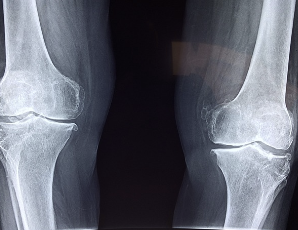

글루코사민 콘드로이친 msm 효능 및 부작용 적정섭취량 등 관련 정보 알아보도록 하겠습니다. 관절은 뼈와 뼈 사이에 위치한 연결점으로, 우리 몸을 움직이기 위한 중요한 부분입니다. 관절은 뼈의 끝에 위치한 연골과 뼈를 연결하는 인대로 이루어져 있으며, 이러한 구조는 원활한 움직임을 가능하게 합니다. 하지만 연령이 들어가거나 부상 등으로 인해 관절의 기능이 손상되면 관절염과 같은 질환으로 발생할 수 있습니다. 이러한 질환은 관절 통증, 감각 이상, 염증 및 손상 등을 일으키며, 일상생활에서의 움직임과 활동에 지장을 주어 생활의 질을 저하시킵니다. 이에 따라 적절한 치료와 예방이 필요하며, 영양소와 운동 등을 통한 관리가 중요합니다.

글루코사민은 연골을 유지하는 데 필요한 성분으로, 연골 조직의 생산과 수리를 돕습니다. 또한 관절염 등의 관절 질환으로 인한 통증 및 염증을 완화하는데도 효과적입니다. 또한 연골 조직의 건강을 유지함으로써, 무릎 퇴행성 질환의 발생을 예방하고 뼈 건강에도 도움을 줄 수 있습니다.

5. 골관절염 예방: 콘드로이친은 골관절염 발병 가능성을 낮추어 주며, 연골 건강을 유지하는 데 도움을 줄 수 있습니다.